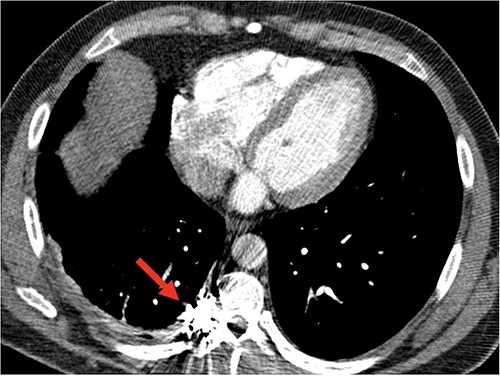

After stabilization, patient was sent to interventional radiology for transcatheter angiographic embolization (TAE) of the T9 intercostal artery. On angiography, the intercostal artery aneurysm was associated with an arteriovenous malformation with venous outflow into the intercostal vein and azygos vein. Therefore, patient has an aneurysm and arteriovenous malformation. The patient underwent a successful coil embolization of the venous outflow, with no filling noted at the completion of the procedure (Fig. 2).

Angiography of T9 intercostal artery aneurysm with successful coil embolization of T9 intercostal artery aneurysm.